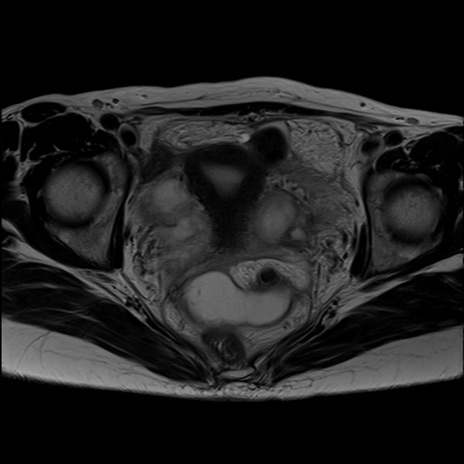

症例39 T2WI(横断像)

MRI(4日後)